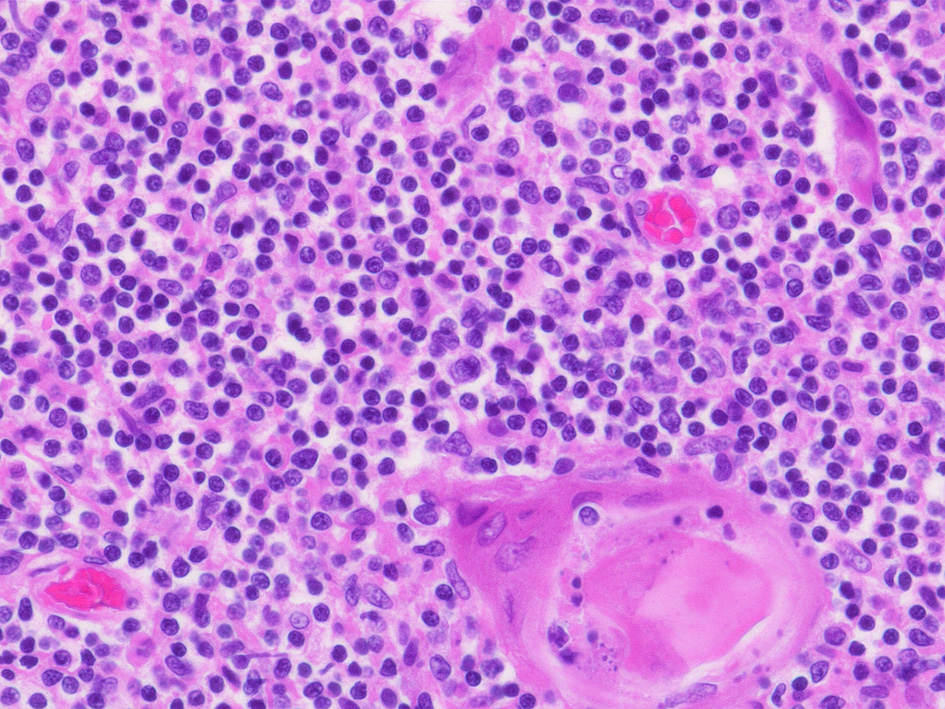

左右二葉の胸腺は, 小葉構造をとり各小葉は分化途上のT細胞に相当する小リンパ球(胸腺細胞; thymocyte)が密に存在する皮質(cortex)と小葉中央部に存在する, 皮質と比較してリンパ球密度の低い髄質(medulla)から構成される。

髄質のリンパ球は大リンパ球が多く, 皮質リンパ球より細胞質に富む.髄質はHEで明るく見える. 髄質にはHassal小体(上図,右下)が散在している.

髄質のリンパ球密度は皮質より低くリンパ球はほとんどが大リンパ球で皮質リンパ球より細胞質に富む.髄質はHEで明るく見える.